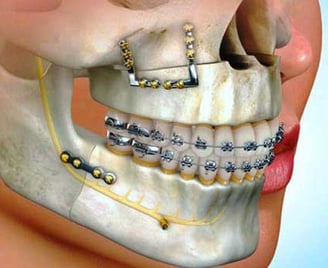

Oral and Maxillofacial Surgery

This specialty includes the diagnosis and surgical treatment of diseases, injuries, and defects of the mouth, jaws, and face, such as tooth extractions and corrective jaw surgeries.